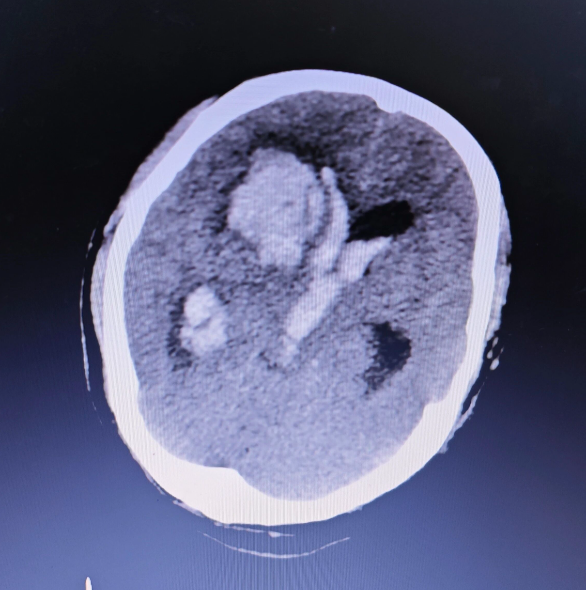

“患者33岁,突发剧烈头痛伴呕吐,意识模糊进行性加重,CT提示脑出血并脑疝形成!”急促的急诊呼叫打破了医院的平静,一场与死神竞速的生命救援即刻启动。

对于正值壮年的90后患者而言,脑出血合并脑疝堪称“致命危机”,脑组织受压移位若不及时干预,短时间内便可能导致呼吸心跳骤停。重症医学科一边快速评估患者生命体征、一边紧急请神经外科会诊、完善术前检查,一边与家属高效沟通病情与手术方案。

术前